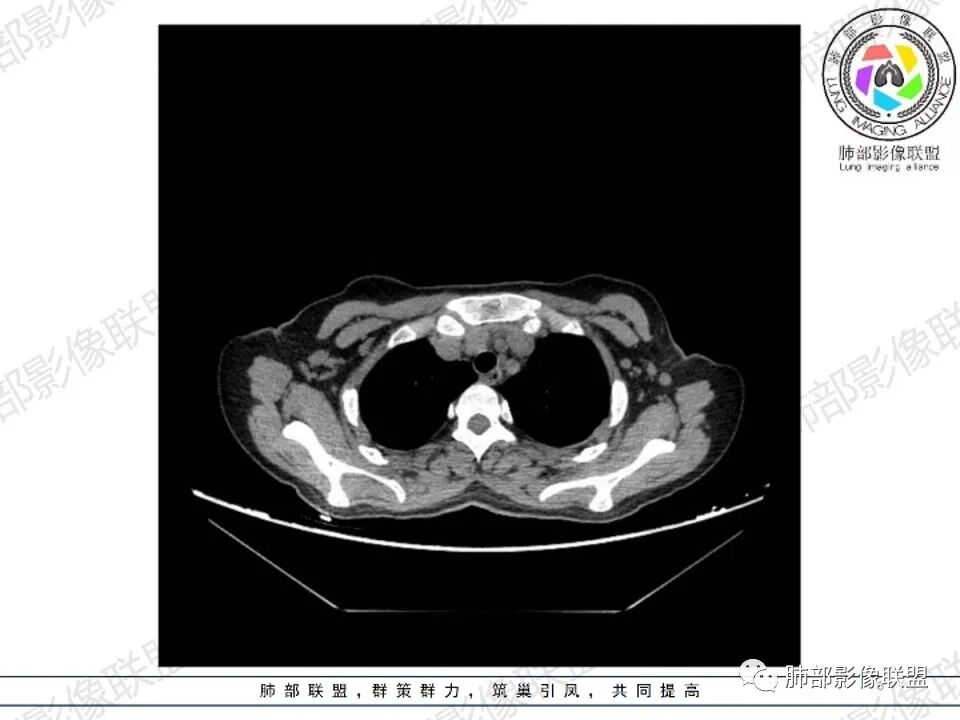

女,27,间断头晕、乏力3年,左眼视物模糊2月。贫血。胸部CT:前纵隔不规则肿块,多结节融合,边界不清,沿主动脉及肺动脉间隙生长,平扫密度欠均匀,增强扫描可见多发低密度坏死,纵隔血管供血穿行,腋窝多发大小不等淋巴结肿大。考虑恶性病变,胸腺癌?肉瘤?淋巴瘤?鉴别胸腺瘤、结节病等。

临床:年轻女性,慢性病程,多系统病变,头晕,贫血,视物模糊。

CT:定位纵膈病变,前中纵隔多发肿块,质软,塑形,密度不均匀,边界清楚。增强不均匀强化,坏死边界清楚,血管漂浮征。双侧腋下多组淋巴结肿大,明显异常强化。

考虑淋巴瘤可能。

2.影像显示前纵隔不规则块状影,依势贴附心脏大血管旁,密度不均,边界不甚清楚,有结节融合感。

3.病灶轻度不均匀强化,可见血管穿行,散在液性低密度区。

双肺门未见肿大淋巴结。

4.双侧腋窝区见增大淋巴结,边界清楚。